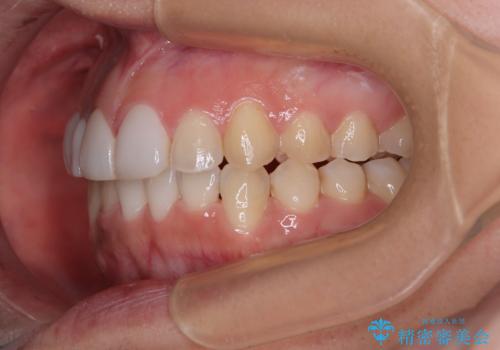

前歯のデコボコが気になる インビザラインによる矯正治療

- 上下前歯のデコボコを気にして来院された患者様です。

インビザラインによる上下歯列の拡大と、IPR(歯と歯の間を削る)にるスペースの獲得により、前歯のデコボコを改善することとしました。

下顎前歯は後戻りを起こしやすいため、舌側を細いワイヤーで固定し、マウスピース型リテーナーで保定を行うこととしました。